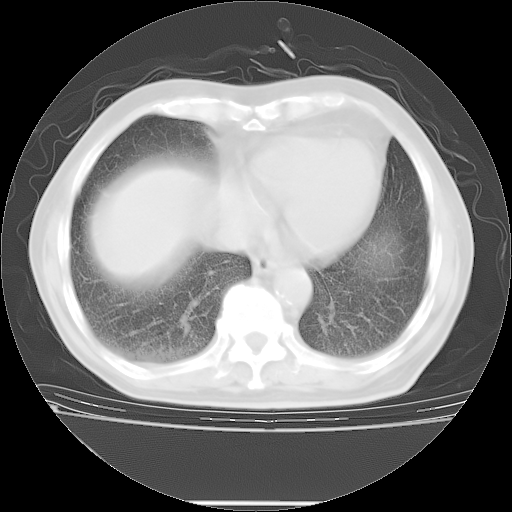

今天复查肺部CT,发现双肺广泛磨玻璃样改变。所以我把3月19日和5月9日相隔50天的肺部CT上传。请大家会诊。

5月9日肺部CT(在4月27日齐鲁医院肺部CT描述部分肺组织磨玻璃样改变,12天后肺组织广泛磨玻璃样改变)

2009年5月9日肺部CT

大致读了系列胸部CT:纵隔窗无明显异常,肺窗:从4、27至今:主要是双肺中下野外带可见毛玻璃样改变,目前处于急性肺泡炎阶段,至于原因考虑1、结替组织或胶原血管性疾病所致?2、恶性疾病如恶组在肺部所致的表现或细支气管肺泡癌?3、药物或其它原因如肺蛋白沉着症所致肺泡炎目前不太可能?总之,明天就去请我院的呼吸科、感染科、血液科和临免专家会诊哈。